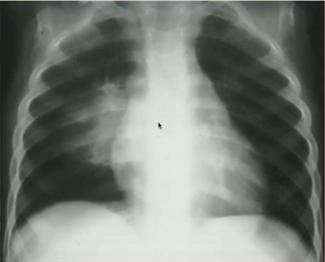

图6.新生儿暂时性呼吸增快症(左:生后胸片;右:生后20小时胸片)Example3 主诉:足月新生儿高热,胎膜早破

胸片特点:“马克笔样“弥漫颗粒、团块状阴影;50%伴胸膜积液。

诊断:新生儿肺炎(B组链球菌肺炎):常见于胎膜早破,母亲阴道感染;影像学表现多样,应结合病史及临床表现与TTN、RDS鉴别。

图7.新生儿B组链球菌肺炎Example4 主诉:过期产儿出生后呼吸困难